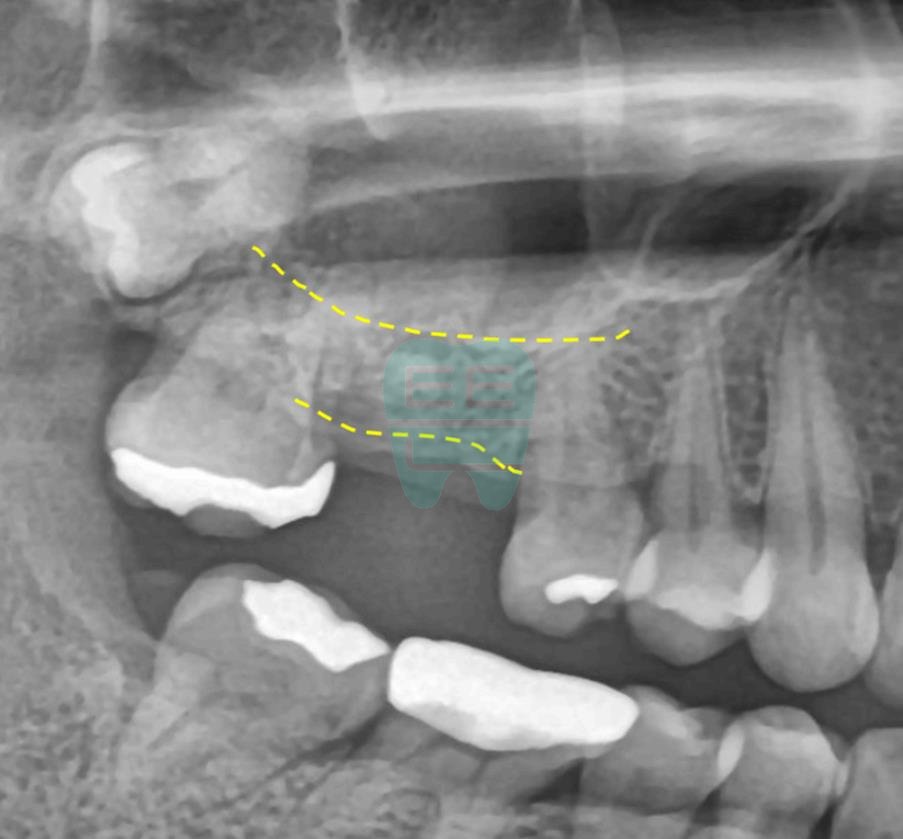

**Pre-operative Panoramic X-ray** — Confirming proximity to the maxillary sinus.

**Pre-operative CT Scan** — Insufficient bone height confirmed, sinus augmentation indicated.